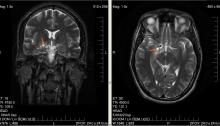

Radiofréquences : un risque accru de cancer pour les militaires ?

Source : Israeli Soldiers Working With Radar Face Higher Risk of Cancer, Israeli Study Suggests – 20/03/2018 – haaretz.com Auteur : Ido Ifrati Une étude scientifique a constaté que le risque de développer un cancer était plus grand chez les soldats qui étaient exposés aux radiations de type radiofréquences. Les soldats qui opèrent en tant…